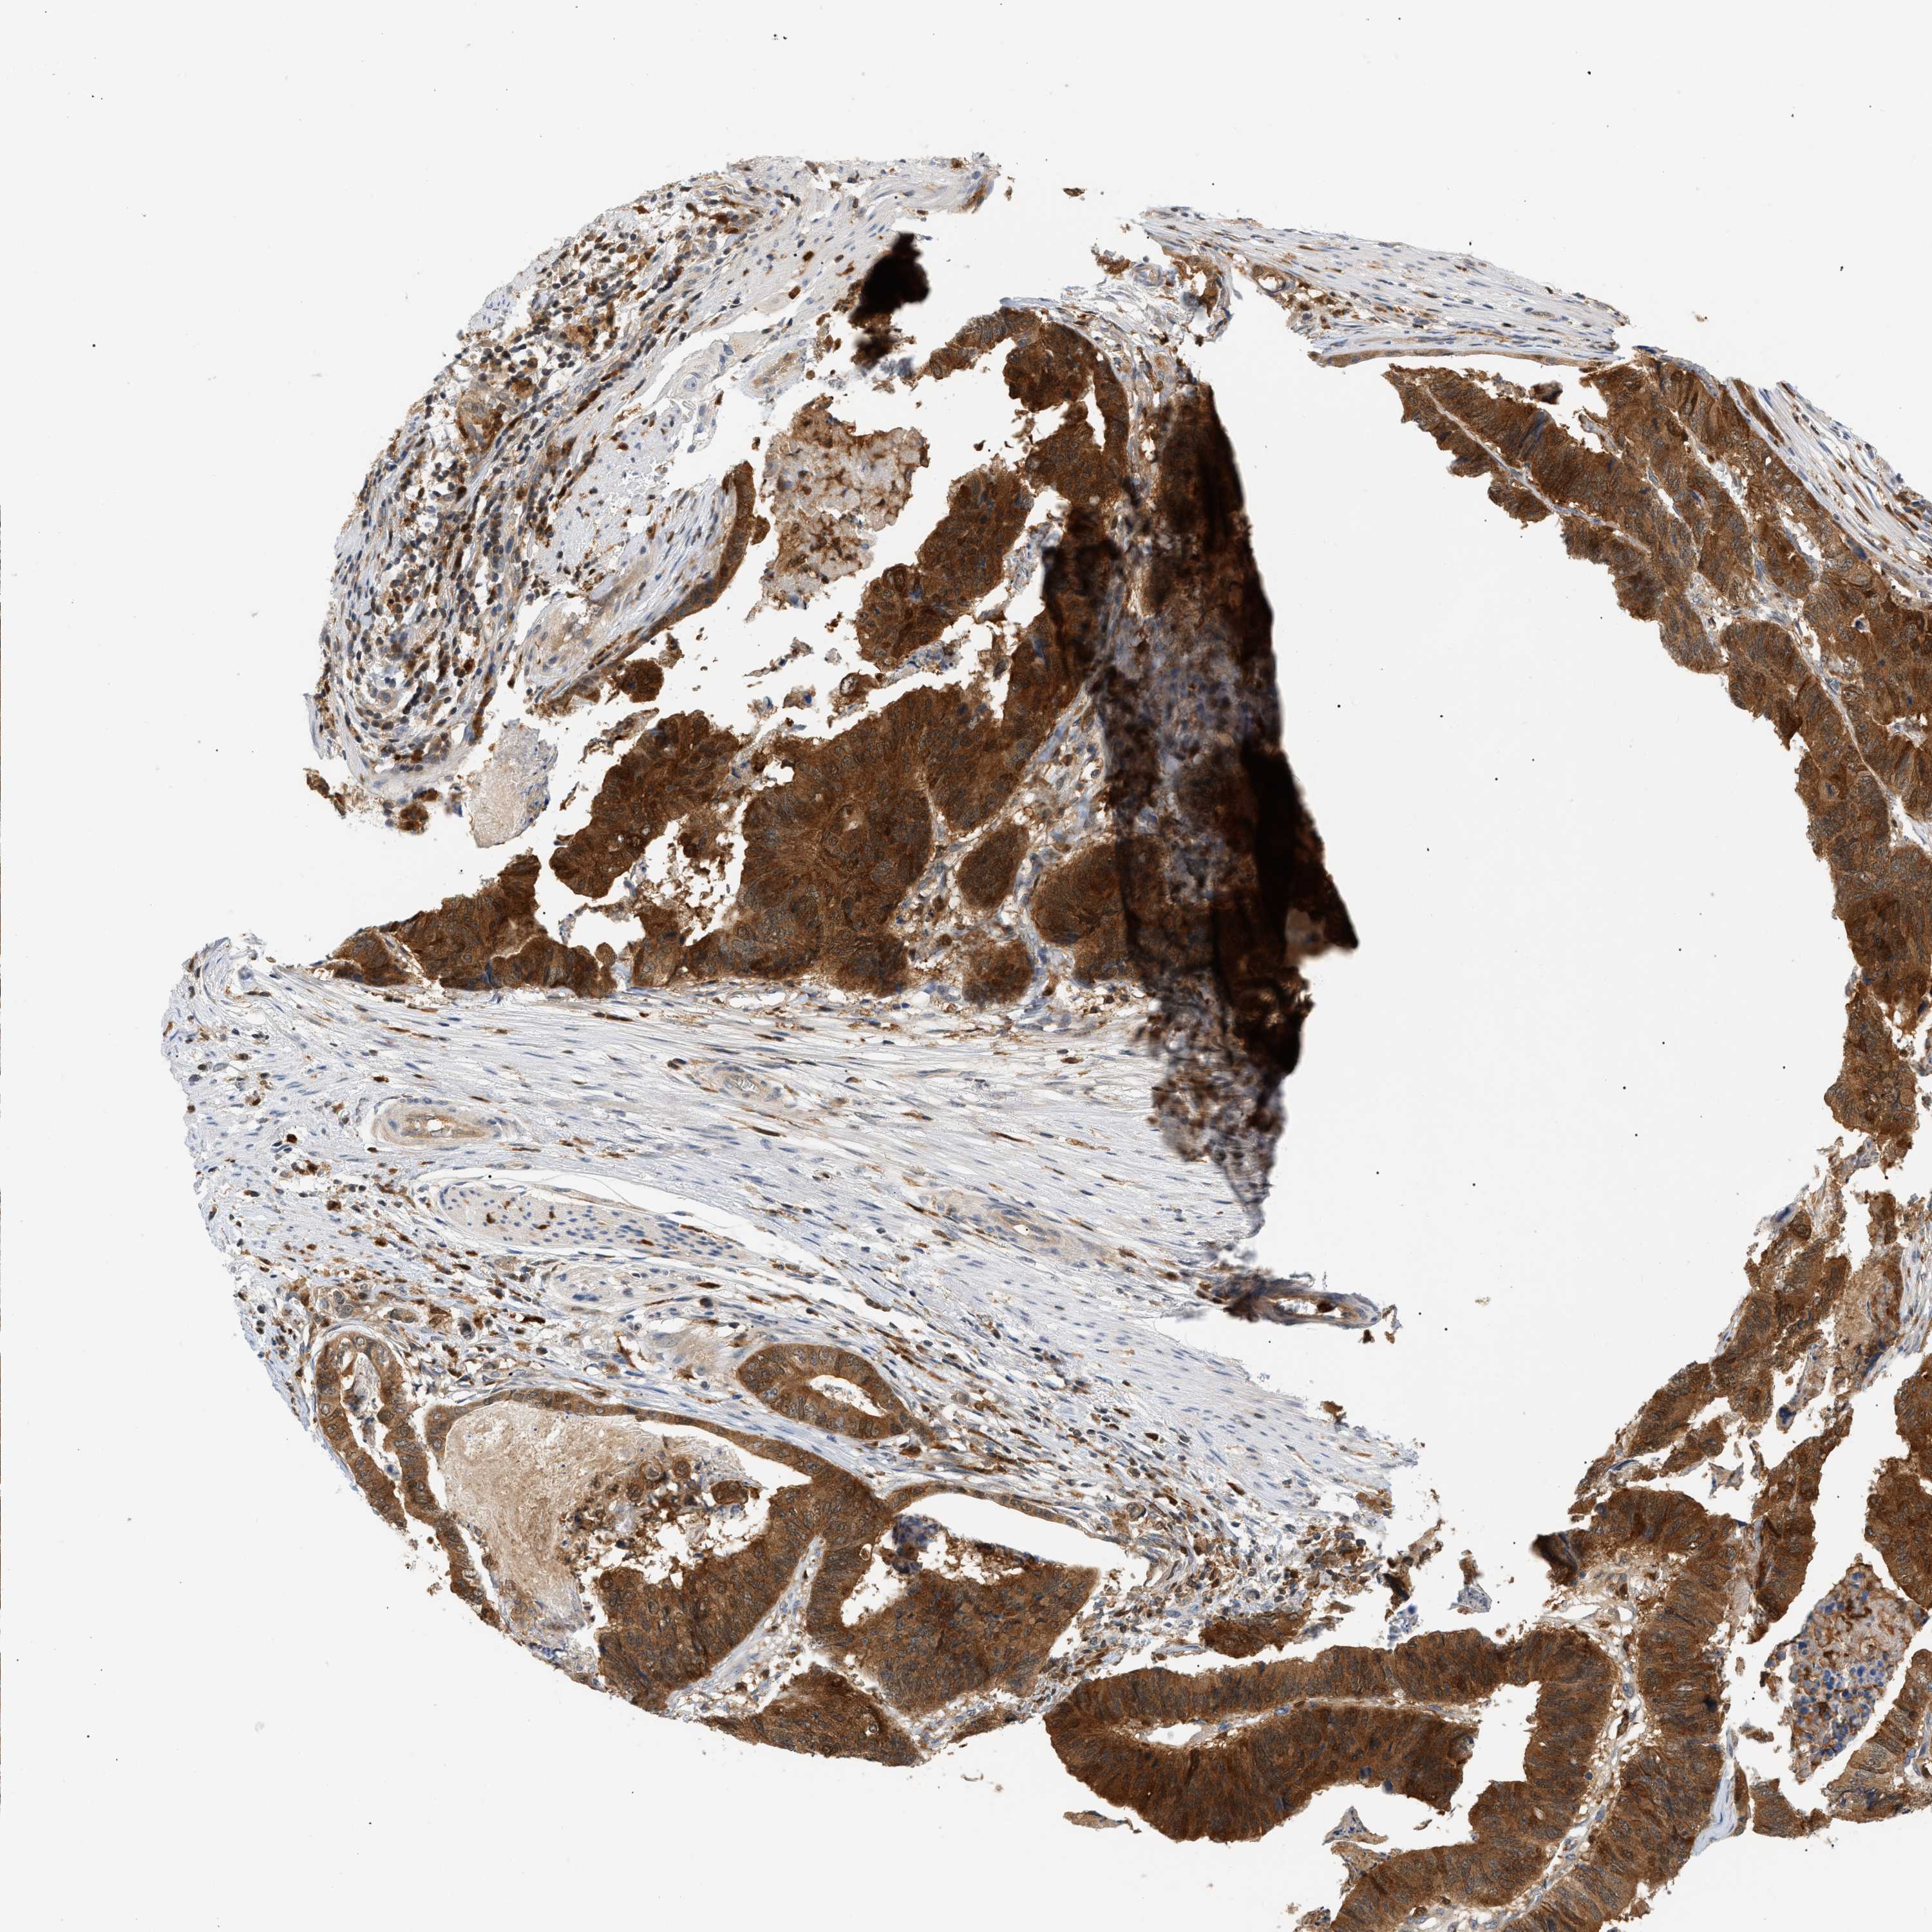

STOMACH CANCER - Protein expressioni

A mouse-over function shows sample information and annotation data. Click on an image to view it in a full screen mode. Samples can be filtered based on level of antibody staining by selecting one or several of the following categories: high, medium, low and not detected. The assay and annotation is described here.

Note that samples used for immunohistochemistry by the Human Protein Atlas do not correspond to samples in the TCGA dataset.

Antibody stainingi

Antibody staining in the annotated cell types in the current human tissue is reported as not detected, low, medium, or high, based on conventional immunohistochemistry profiling in selected tissues. This score is based on the combination of the staining intensity and fraction of stained cells.

Each image is clickable and will lead to virtual microscopy that enables deeper exploration of all samples and also displays staining intensity scores, fraction scores and subcellular localization as well as patient and tissue information for each sample.

Antibody HPA049074

Antibody HPA054496

Antibody CAB006853

Antibody CAB015948

Staining

High

Medium

Low

Not detected

Intensity

Strong

Moderate

Weak

Negative

Quantity

>75%

75%-25%

<25%

None

Location

Nuclear

Cytoplasmic/membranous

Cytoplasmic/membranous,nuclear

Adenocarcinoma, NOS

Adenocarcinoma, High grade